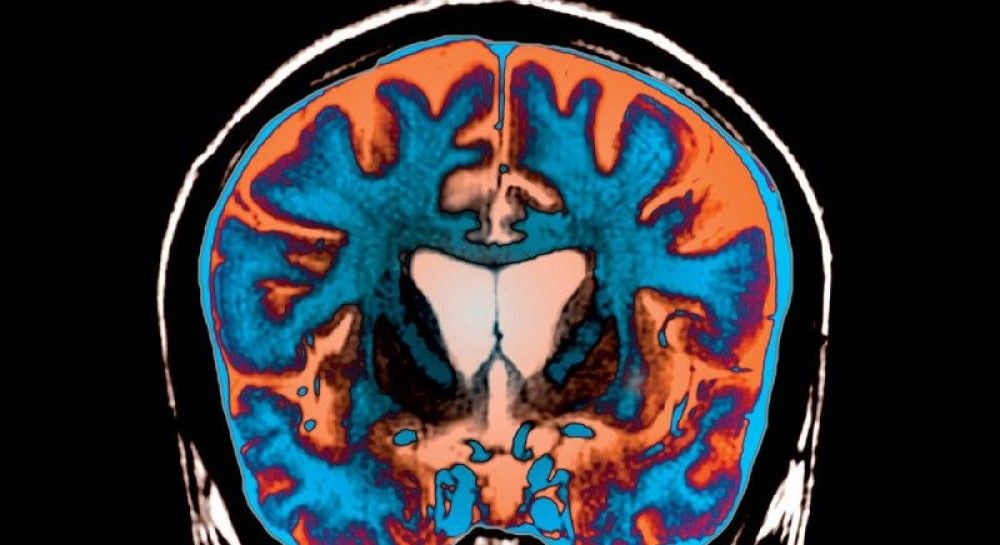

Людський мозок з пробірки може стати розумнішим, ніж природний